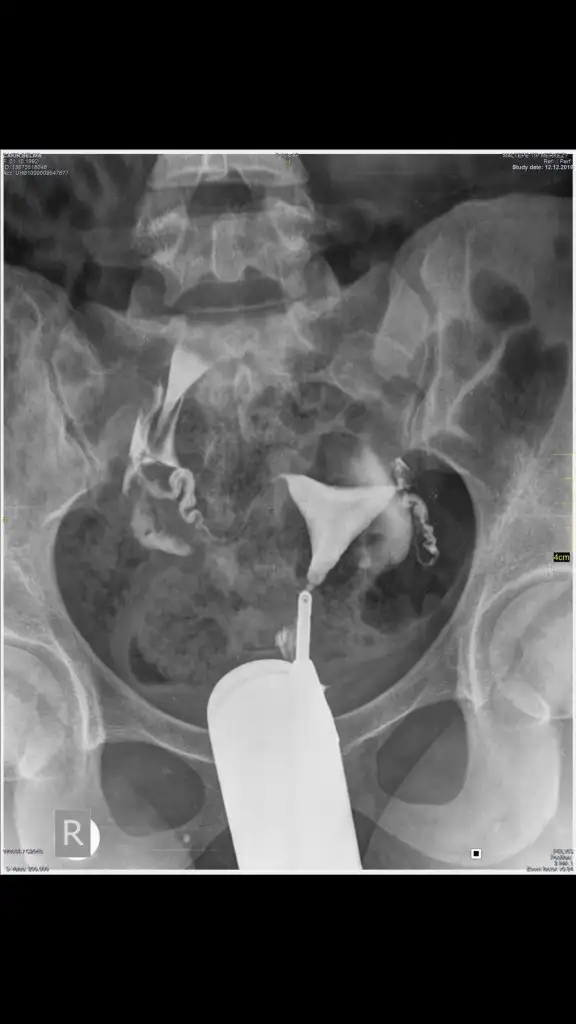

Memnunum canım. Bu iğne menapoza yakın olanlarda kullanılıyor. Benim de amhıma göre bile az çıkmıştı ya yumurtam bunu da ekleyeceğiz o yüzden. 40 yaş üstü tüp bebek topiği var ya ordakiler kullanıyor genelde.Canım bu iğneyi ben ilk defa duydum inşallah senin için hayrlı bir tedavi olur doktorundan memnun musun

Senin şeklinde problem yokmuş ama o sıvı dağılma kısımlarını anlayamıyom ben tabi kiCanm bunu şmdi gördüm elimde yoktu benm CD şeklindydi ameliyat günü elden istediler uğraştırdılar beni